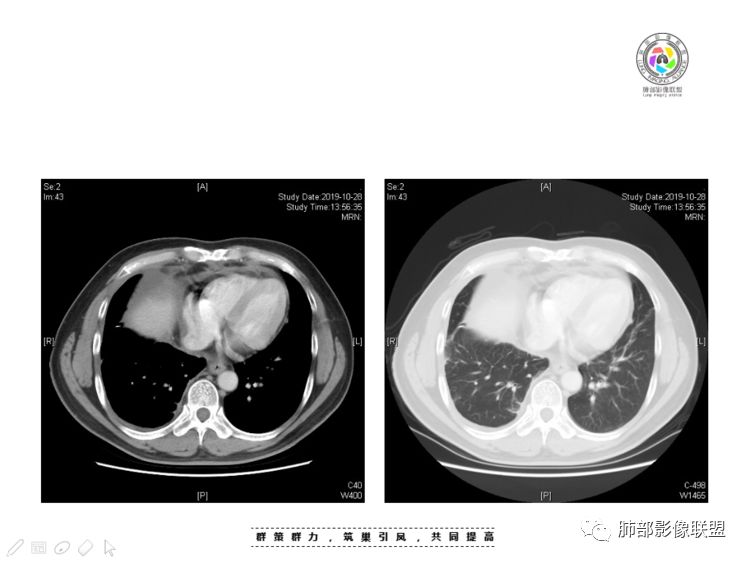

穿越七海的风:右前纵隔占位,恶性肿瘤,生殖来源?右肺实变是占位or肺不张?考虑为部分肺不张FeNo:右前纵隔占位,右肺结节,胸膜凹陷,小尾巴,右肺不张,考虑恶性杨旭华:恶性,前纵隔肿物,与血管关系密切,上腔静脉变窄,右肺野一元论考虑叶间裂增厚,恶性胸膜间皮瘤可能大小丽:到底是纵隔来源还是胸膜来源?我怎么倾向于胸膜来源,和叶间胸膜关系密切,而且纵隔内上腔静脉是向内侧推移。胸膜肿瘤(间皮瘤?SFT?)包裹性胸腔积液?马春平(张家港市一院胸外科):前纵隔占位,左无名受压,右大量胸腔积液可能是胸导管汇入处侵犯受压,考虑纵隔鳞癌孙冰伟:右上纵隔占位,也感觉和叶间胸膜关系密切,右侧胸膜局限性增厚,考虑恶性可能性大灵:前纵隔占位,血性胸水,胸膜凹凸不平,查见肿瘤细胞,结合免疫组化考虑胸腺癌。鉴别胸膜间皮瘤。采莲:右前上纵膈旁可见类圆形肿块,纵隔血管内移,感觉来源于胸膜,肿块内密度低,似水样密度,右侧胸膜广泛增厚,少量胸腔积液。心包少量积液。考虑胸膜间皮瘤,鉴别肺癌并胸膜转移?水晶石头:患者中年男性,胸闷15天。有“高血压、慢性肾小球肾炎”病史。查肿瘤标志物正常,胸水提示渗出液,胸水病理查见瘤细胞。胸部CT:右肺上叶后段结节、斑片影,见胸膜牵拉、包裹积液及部分纤维条索灶,似见卫星灶,右侧胸膜增厚。前纵隔脂肪密度增厚,右侧可见类圆形低密度(液体)肿块,边缘光滑。综合考虑右肺腺癌并胸膜转移,结核可能。周太狼:考虑纵隔胸膜来源肿瘤,恶性,胸膜间皮瘤伴转移?徐飞:中年男性,影像为右侧胸腔及叶间积液,叶间胸膜增厚轻度强化。前纵隔右侧心缘旁团块,可见坏死。胸水见癌细胞,综合考虑恶性,胸腺癌伴转移。小赵:中年男性,血性胸水,常规查见癌细胞,李凡他实验阳性。胸部CT示前纵隔见不均匀密度影,与邻近大血管分界不清,囊变坏死明显,增强扫描呈不均匀强化,心包及右侧胸膜增厚,并心包及右侧胸腔少量积液。综合考虑胸腺癌。右肺中叶病变周围见多发纤维条索,支气管部分进入病灶,考虑炎性病变。流心明智:患者,男性,50岁。胸闷15天。高血压20年,慢性肾小球肾炎15年。肿标正常,胸水提示渗出液,胸水查见癌细胞。胸部CT:右肺肿块影,斑片影,索条影,可见胸膜牵拉、多发包裹积液,纵隔上腔静脉受累,心包受累。综合考虑:ROSE似腺?考虑右肺腺癌并胸膜转移,心包受累。鉴别胸腺Ca、淋巴瘤,纵隔病变不懂,等老师们精彩分析。王秀仙:前纵膈囊实性肿块,与纵膈分界不清,心脏大血管及上腔静脉受压向内后移,右侧后胸膜、侧胸膜增厚,右侧叶间裂不规则增厚,心包积液,根据腔静脉移位情况,考虑纵膈胸膜来源恶性肿瘤,胸膜间皮瘤?鉴别胸腺癌并胸膜转移。高广飞:上纵隔占位,右侧叶间胸腔积液,需考虑恶性自信人生:多发囊实性病灶,包裹性积液,考虑胸膜来源 只是没有看到壁结节,恶性胸膜间皮瘤巴伟:前上纵隔占位,胸膜及心包结节,考虑胸腺瘤或癌,右肺病灶,先考虑陈旧炎性病变。Lenle董:前纵隔占位,部分边缘模糊,病灶内囊变?坏死?上腔静脉受侵,考虑胸腺癌;叶间片状影,强化明显,炎性考虑。常志强:前纵隔囊实混杂密度肿块,边界不清,实性部分强化明显,结合胸水内见癌细胞,考虑恶性肿瘤伴转移。飞鹰行动:前纵隔占位,软组织密度及囊性密度,实性部分密度均匀,致密,病灶与周围血管分界不清,增强后病灶强化有类似不温不火强化,部分血管受侵犯,右肺见肿块样病变及条索状病变,一元论,考虑淋巴瘤,二元论,考虑胸腺瘤B2—B3伴右肺病变。尽量一元论考虑,淋巴瘤可能。看图说话:右肺索条病灶,边缘膨隆,胸膜牵拉,考虑右肺癌伴胸膜转移。晨:前纵隔囊实性肿块,与纵隔分界不清,右侧后胸膜、侧胸膜增厚,右侧叶间裂不规则增厚,考虑纵隔胸膜来源恶性肿瘤,考虑胸腺癌并胸膜转移。丽:中年男性,前纵隔囊实性肿块,呈偏心性生长,临近大血管受压推移,增强后实性部分不均匀强化,心包可见条形积液,考虑胸膜来源恶性肿瘤,胸腺癌可能大。另右肺多发斑片状高密度影及实变密度影,实变影呈均匀强化,右侧胸膜局限性增厚,考虑炎性病变。小飞:右前纵隔囊实性占位,实性部分明显强化,右侧叶间胸膜增厚,右侧胸腔积液,心包积液,考虑恶性胸腺瘤!尘缘:支持恶性胸腺瘤(囊实性肿块,实性强化,且侵犯纵隔,脂肪间隙模糊)伴肺内及胸膜转移。浪迹天涯:考虑侵袭性胸腺瘤——胸腺前纵隔占位,周围脂肪间隙模糊不清。尘缘:不除外另一种可能:二元,肺内腺癌合并胸膜转移,纵隔的畸胎瘤可能。一米阳光:晨读中年男性,右肺结节影,叶间裂及胸膜增厚牵拉,右侧胸水。心包多发结节改变。胸水查见癌细胞。考虑,腺癌并转移。鉴别,胸膜间皮瘤并转移前纵隔囊实性占位,二元考虑。心灵鸡汤:老年男性,右肺中叶外段长条状软组织密度影,边缘膨隆,邻近胸膜牵拉,部分胸膜有栽脏,右中叶外侧段支气管堵塞,常规考虑恶性肿瘤,腺癌可能,结核、鳞癌不除外,另右肺上叶斑片影,小叶性肺不张?右前纵隔囊实性不规则形密度影,其内见部分脂肪样极低密度影,与邻近血管边界不清,心包外膜有侵犯,增强未见纵隔窗平扫,实性及分隔见增化,其内低密度影未强化,考虑低度恶性纵隔肿瘤,间皮瘤可能,畸胎瘤、淋巴瘤待排,建议支气管镜及穿刺活检。曹志勇:右前纵隔考虑来源于胸膜的恶性肿瘤,右肺内病灶考虑鳞癌,二元德芙~云味:中年男性,右肺见结节、斑片影,右侧包裹积液、胸膜牵拉,纤维条索,前纵隔囊性占位,考虑腺癌、并转移。欧阳英:右前中纵隔囊实性肿块及右肺内结节灶,支持恶性肿瘤,胸腺癌并肺内转移可能张延军:前纵隔见不规则软组织影,密度不均,右侧缘见囊变区,纵膈及侧胸壁胸膜增厚,增强呈不均匀强化,右肺中叶见结节灶,近段支气管阻塞,叶间胸膜不规则增厚,考虑1:右肺中叶腺癌伴纵膈及胸膜转移;2:前纵膈侵袭性胸腺瘤并胸膜侵犯,中叶炎性改变?彭君:老年,前纵隔占位 ,坏死边缘清, 侵犯心包 右侧胸膜及叶间胸膜结节 ,少量胸水, cea不高 ,考虑恶性, 间皮瘤可能 ,转移待除外。毛勤香:恶性没问题,胸水查见癌细胞,一元还是2元,右肺中叶肿块,边缘毛糙,局部似有毛刺,周围有粘连,右侧胸膜腔少量积液,胸膜增厚多发结节,含叶间裂结节,纵膈脂肪间隙模糊,纵膈胸膜增厚,心包增厚积液,右前那个类圆形低密度肿块,纵膈血管内移,我考虑胸膜来源可能性大,综合考虑,一元肺腺癌并多发转移,二元考虑胸膜间皮瘤并多发转移,肺内炎症不张。

Coke with ice:囊性部分考虑包裹性积液?南边:不是积液;有间隔;张力高;而且位置有些特殊

我认为囊张力高,积液中的气体均在周围,外侧、下方,囊内有间隔:各腔密度不一致;提示:囊腔属于前纵隔,不是包裹性积液;现在的问题:囊腔与内侧的病灶是否是一体的

本例纵隔与肺内两处病变,回顾总结分析:

1、右肺内病灶,病灶呈结节样,边缘欠规则,局部膨隆,叶间裂胸膜牵拉凹陷,再看相应支气管腔堵塞截断,临床资料胸水中查到癌细胞,均提示病灶倾向恶性,腺癌的病理意见与之相吻合。

黄勇老师总结,腺癌如果与胸膜、叶间裂紧贴或伴胸膜凹陷,胸膜、叶间裂多发结节,应当高度怀疑腺癌转移。

2、前纵隔内病灶囊实性混杂密度病灶,囊性病灶主要位于右侧,张力较高,有分隔影,囊壁右侧缘光整,病灶左侧实性部分边界不清明显强化,病灶肺瘤交界面大部分边界清楚,部分模糊。

胸腺瘤/胸腺癌:病灶内那么大的囊,常规考虑B型以上胸腺瘤,囊内有分隔影,病灶周围脂肪间隙模糊,常规考虑侵袭性胸腺瘤或胸腺癌,若侵袭性胸腺瘤,常侵犯胸膜、心包,很少累及肺。胸腺癌易侵犯胸膜、肺并纵隔淋巴结及远处转移。但肺内腺癌形态更符合原发灶。胸膜及叶间裂转移则即可来自肺,也可来自胸腺癌。

尽管前纵隔病灶缺乏相关病理资料,但是小编还是认为肺内与纵隔病灶以二元论解释。只是肺内恶性病灶引发的胸膜改变可能会影响我们对纵隔病灶的判断。